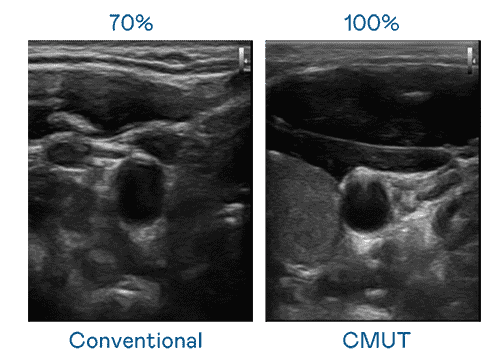

CMUT 技术是一种用电容式微机电元件来产生超音波讯号的技术。。与传统 PZT 压电式技术相比,,CMUT 频宽增加 30%,,更宽频的超音波讯号让影像解析度大幅提升,,是实现高影像品质医疗超音波扫描、、、促进精准医疗发展的关键技术。。

大频宽带来超清晰影像

超音波影像的解析度高低,,,,首先取决于探头能发出的讯号频宽。。银河集团 CMUT 可提供高清晰的超音波讯号,,,提供高频宽、、高灵敏度、、、、影像纹理细节更高的超音波影像,,,,协助医护人员缩短影像判读时间及利用精准的医疗影像进行诊断。。